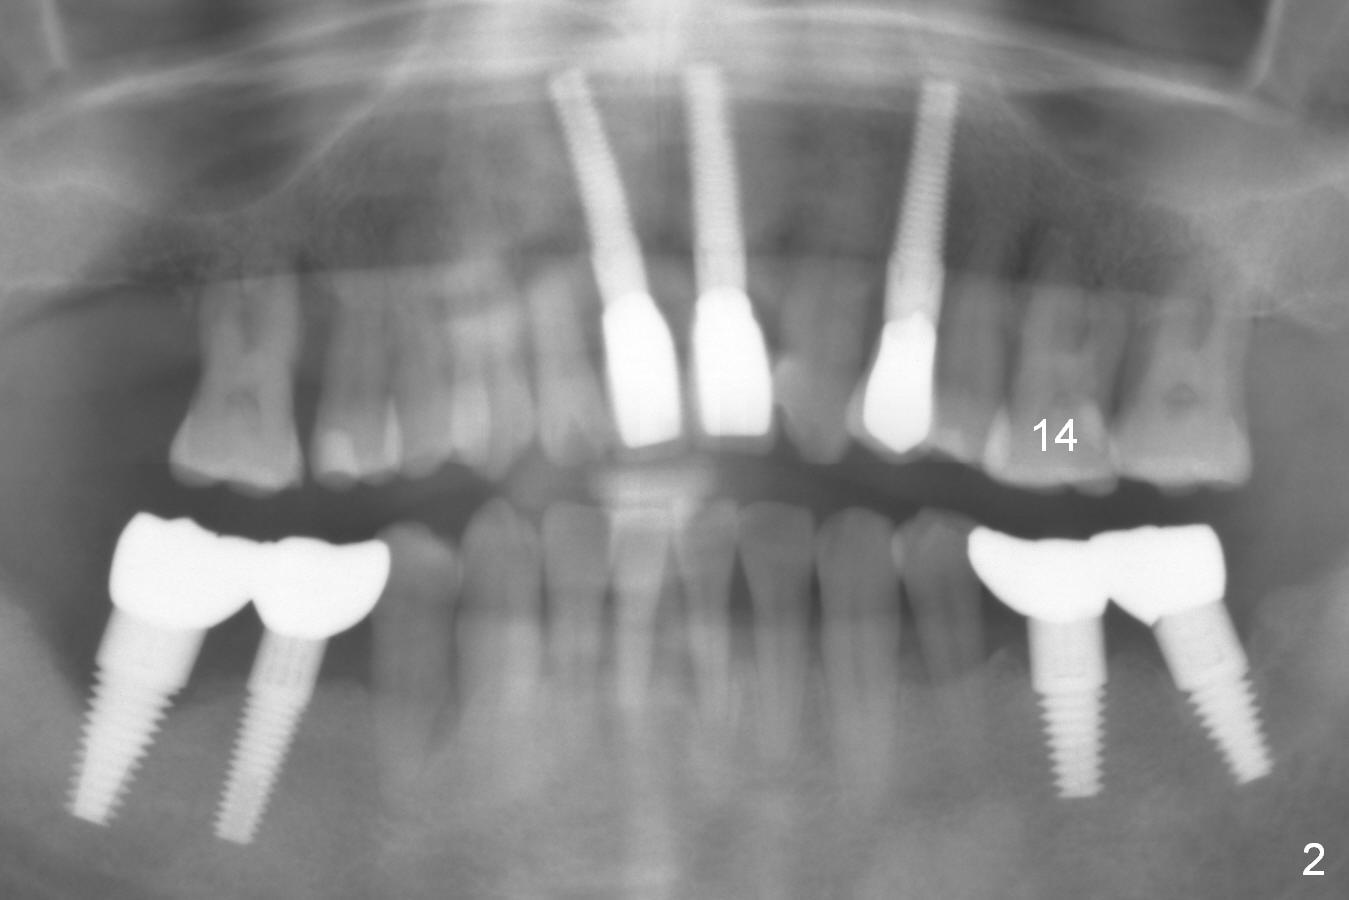

A 44-year-old man is a typical patient with chronic periodontitis (Fig.1). Periimplantitis develops following immediate implant at #31 (Fig.2). The symptom (bleeding) improves after bone graft and use of Water Pik. Now the tooth #14 appears to be non-salvageable because of gingival hemorrhage and deep pockets after previous osseous surgery. To prevent periimplantitis, an immediate implant does not need to be large or long. It has to be placed deep, and in the middle of the native bone, surrounded by bone graft. To facilitate wound healing, draw 3 tubes of blood for PRF. One of them is processed for plug in case of sinus lift. To prevent the buccal gingiva collapse, the buccal portion of the immediate provisional should extend into the socket. If the gingiva is around 4 mm, use IBS implant (Fig.3,4). Otherwise, a SM implant will be used after extraction (Clindamycin), since abutments have cuffs as long as 4.5 and 6 mm so that it is easy to place an implant as deep as possible. Initial depth will be 9 mm (bone-level), followed by Magic Drill (5.3 mm, if possible) and Magic expanders (4.3x10 and 4.8x11 mm, bone density 26-300 units).